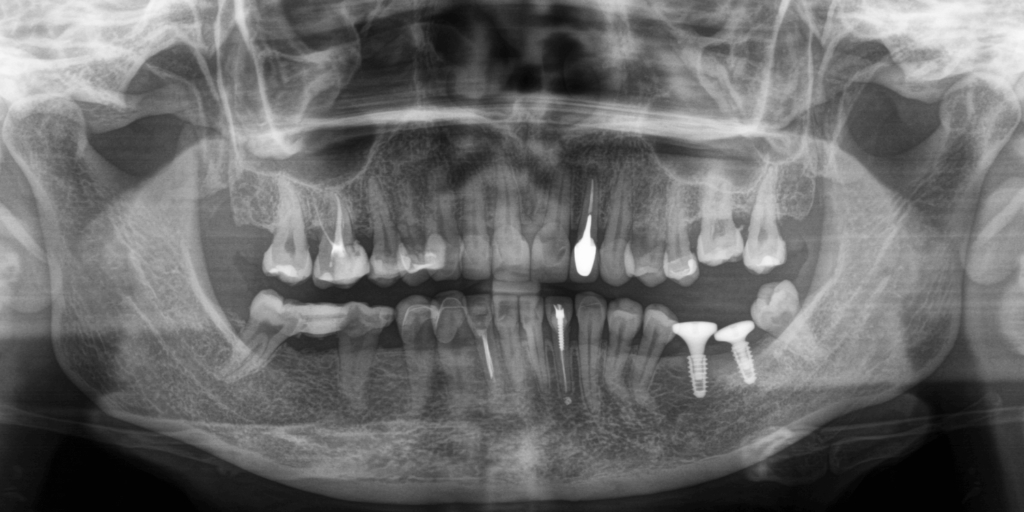

Впервые мы встретились с пациенткой примерно год назад. Тогда она обратилась к нам в клинику для проведения профессиональной гигиены полости рта и были жалобы на отсутствие зубов 6 и 7 на нижней челюсти слева. После КТ-исследования и осмотра обнаружили, что некоторые зубы (ранее протезировавшиеся) уже депульпированы. Практически все зубы были покрыты коронками, полукоронками и винирами. Относительно старые, но в удовлетворительном состоянии. Объем костной ткани позволял провести имплантацию зубов. Предложили установить зубные импланты методом двухэтапной имплантации на место отсутствующих зубов с дальнейшим протезированием цельнокерамическими коронками.

Пациентка согласилась на лечение, но на этапе планирования операции, захотела провести хирургическое вмешательство с применением общего обезболивания ("наркоза") из-за страха боли, однако нашему хирургу удалось договориться с ней об операции по имплантации без применения наркоза. Операция прошла быстро, комфортно и совершенно безболезненно.

Мы выполнили имплантацию "под ключ" и через некоторое время пациентка снова обратилась к нам с запросом на замену старых ортопедических конструкций во фронтальном участке зубного ряда, поскольку хотела зубы немного "более длинной формы", чем у нее были. Врач предложил выполнить работу путем примерки mock-up модели, чтобы учесть все пожелания по размеру и форме зубов, а также, чтобы пациентка могла примерить на себе будущие конструкции и походить с ними определенное время. Из-за интенсивного графика пациентка отказалась от такого предложения и примерки, и отметила, что ее полностью устраивает форма зубов, просто нужно сделать их немного длиннее и очень быстро.